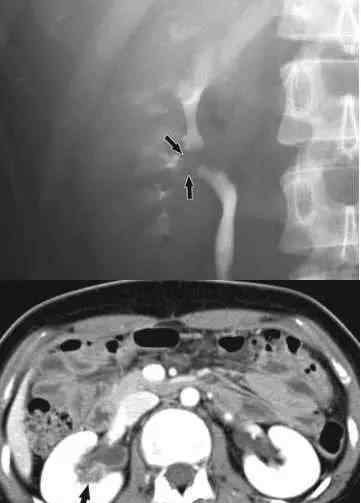

33岁,男士,中重度尿血,左侧腰痛,肾窦静脉血管瘤。

27岁,女士,中重度尿血,肾窦平滑肌瘤